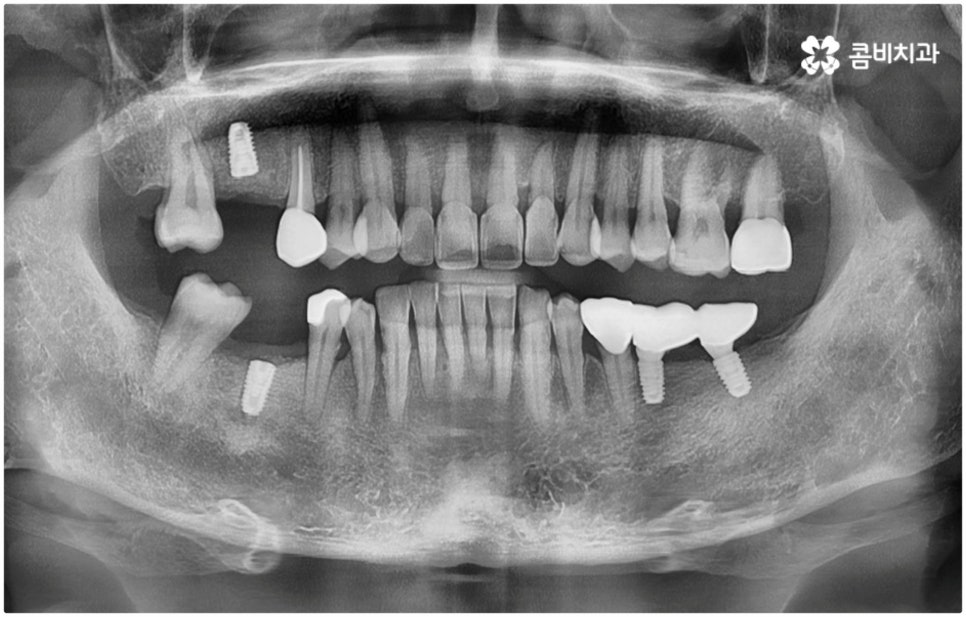

관련 기술의 발달 및 꾸준한 학술 연구를 통해 양질의 임상 데이터가 쌓이고 국산 임플란트 재료가 개발되어 비용적인 부담이 줄어들면서 점차 대중화되기 시작한 임플란트는 현재 치아 상실에 대처하는 가장 대표적인 방법으로 손꼽히고 있어요. 그러나 각각의 상황에 따라 6~8개월, 길게는 1년 까지도 소요될 수 있는 임플란트 시술 기간은 바쁜 현대인들에게 부담으로 다가올 수 있는데요. 업무 등으로 시간 여유가 넉넉하지 않은 경우 임플란트 치료 자체를 망설이는 원인이 되기도 할 거예요. 이럴 때는 발치후 임플란트 즉시 식립 방식을 고려해 볼 수 있어요.

발치후 임플란트 즉시 식립 방식은 다른 임플란트와 달리 치아가 탈락한 빈 자리에 곧바로, 또는 조금 남아있던 뿌리를 뽑은 후 그 자리에 그대로 임플란트를 심기 때문에 공백 기간이 단축될 수 있고 임시치아 제작을 통해 해당 기간 동안 임시 틀니를 사용해야 하는 데서 오는 불편함 및 심미적인 어색함도 해결할 수 있어요. 또한 환자분들의 입장에서 마취 한 번에 발치와 식립 두 가지 과정이 함께 이뤄지기 때문에 통증과 두려움이 감소되고 치과에 내원해야 하는 횟수도 줄어들어 번거로움이 덜 할 수 있습니다.

치아가 빠진 순간부터 이를 받치고 있던 치조골이 서서히 흡수되기 시작하므로 영구치가 빠지고 나서 시간이 많이 지나게 되면 부족한 잇몸뼈 부분을 뼈이식으로 보충해 주는 과정이 추가적으로 들어가야 하지만 이미 뼈가 손상된 경우가 아니라면, 즉시 식립을 하면 그럴 필요가 없는 거예요. 또한 잇몸이 이미 내려앉은 후 수복을 하려면 잇몸 라인이 인위적으로 만들어질 가능성이 높아지는데 치조골 소실이 크게 일어나기 전에 임플란트를 심게 되면 주변 치아 및 잇몸과 보다 조화롭게 맞출 수 있어서 심미적인 부담도 덜 수 있어요.

발치후 임플란트 식립까지 회복 기간을 두지 않고 즉시 심게 되면 원래 치아가 있던 자리를 육안으로 확인한 후 그 자리에 곧바로 식립하므로 보다 정확한 위치를 잡을 수 있다는 장점도 있습니다. 하루 만에 식립과 임시치아까지 장착이 가능하여 간단한 식사도 할 수있다는 점에서 원데이 임플란트라고도 불리는 즉시 식립 방식은 지금까지 알아본 바와 같이 여러 장점을 가지고 있기 때문에 많은 분들이 선호하시고 있는데요.

하지만 여기서 주의하셔야 할 점은 누구나 발치후 임플란트 를 즉시 식립할 수 있는 것이 아니라 바탕이 되는 잇몸뼈의 양이 충분하고 기존에 염증과 같은 잇몸 질환이 없는 분들의 경우에만 이용할 수 있는 방법이기 때문에 3D CT 등 정밀 분석 기계로 환자분들의 상태를 정확하게 진단한 후에 결정해야 한다는 거예요.

즉, 해당 분야의 임상 경험이 풍부한 숙련된 의료진분들이 계신 치과에서 자신이 발치후 임플란트 즉시 식립 방식이 가능한지 부터 확인하실 필요가 있는데요. 만약 다양한 이유로 인해 발치 후 즉시 심는 것이 불가능한 케이스라고 한다면 상황에 맞게 뼈이식, 상악동 거상술, 잇몸 질환 치료 등 선처치들을 먼저 해 주고 나서 충분한 회복 기간을 두고 임플란트 시술을 진행해야 식립 성공률 및 지속 가능성을 높일 수 있습니다. 이렇게 환자분들 각각의 상황을 고려하지 않은 채 발치 후 즉시 식립을 무리하게 진행하게 되면 임플란트의 위치를 제대로 고정하는 데 어려움이 있어 해당 치아로 잘 씹을 수 없게 되고 얼마 지나지 않아 다시 쓰러지거나 주변 치아와 잇몸에 압박을 가해서 지속적으로 좋지 않은 영향을 주게 되는 등 문제가 커질 수 있으니 주의하실 필요가 있어요.